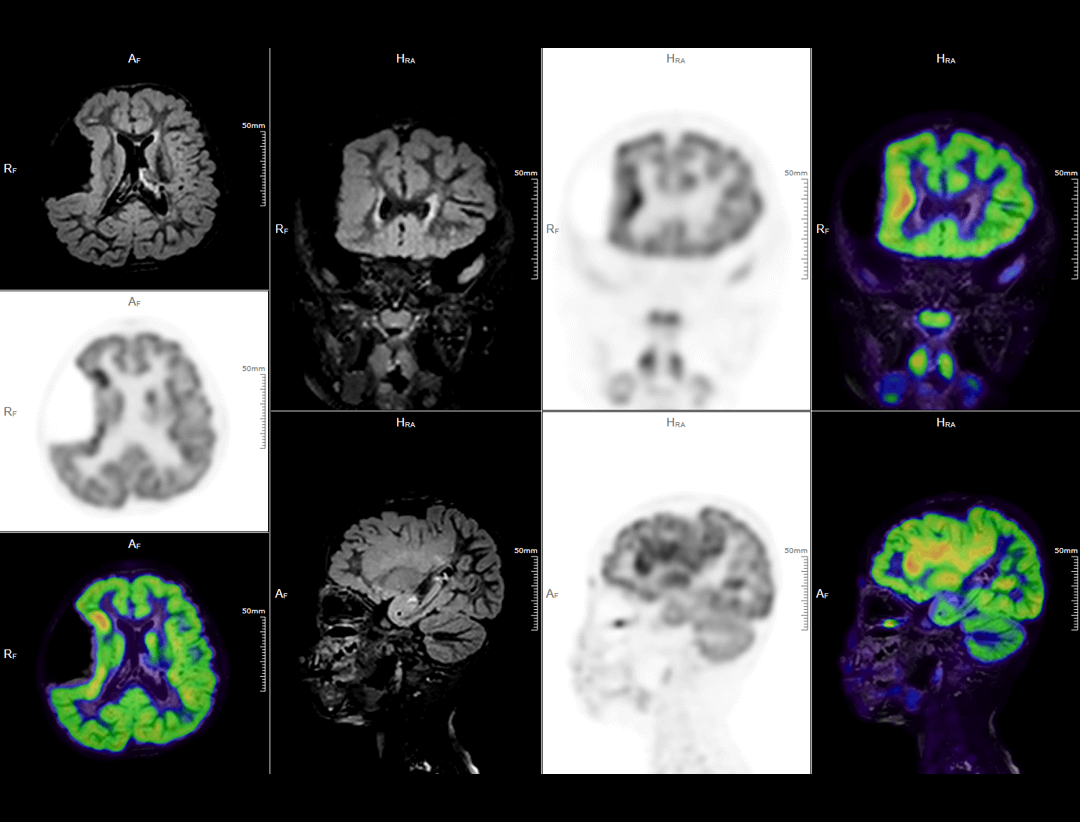

Neuro Imaging

2.8mm NEMA PET Spatial Resolution

定量精度、小さな病巣の検出能を大幅に向上します。